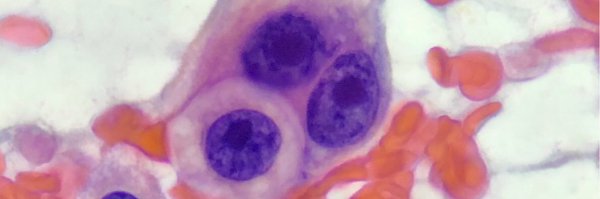

With better pancreatic biopsies available, is there still space for FNA? @MauroSaieg examines where cytology remains a game-changer. @JMP_MDPI #Pancreas #Cytology #MolCytoPath25

Dr @gcai1978 on FNA of cystic lesions of the pancreas- is it still used ? The answer is a robust YES !